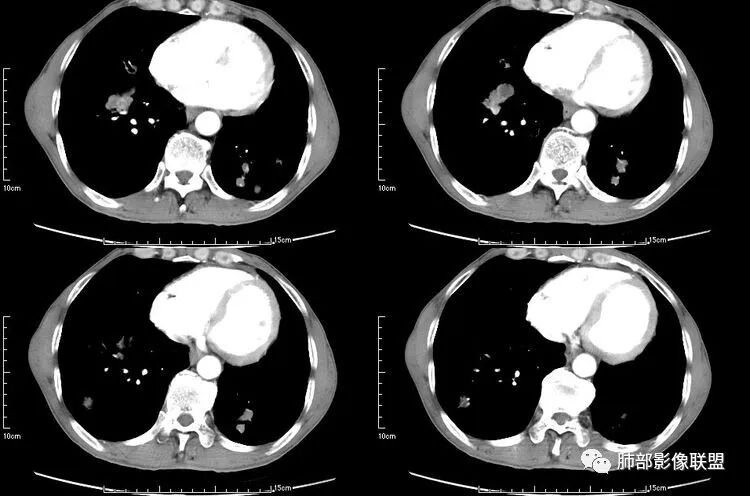

患者老年男性,咳嗽、咳痰、痰中带血伴胸闷2月余。长期大量吸烟史。查肝肾功能、血糖、血脂、心肌酶、电解质、血沉、C反应蛋白、抗“O”、类风湿因子、抗核抗体谱无明显异常。肿瘤标志物提示NSE、CYFRA21-1稍升高。胸部CT:肺气肿背景,左肺下叶后基底段不规则肿块影,见支气管截断,内见大片状低密度区及部分血管影,增强轻度强化,远端空洞形成。双肺多发不规则实性结节影、见毛刺、胸膜牵拉及血管集束,结节内见空洞形成,部分可见血管影,多位于胸膜下。双肺见多发肺大泡。综合考虑左下肺恶性病变并双肺转移。鳞癌或淋巴瘤可能。鉴别血管炎性病变及真菌感染。

左肺下叶团块病灶,有明显张力,增强后病灶内部有可疑延迟强化,看不清楚病灶与支气管的关系,应该支气管受压阻塞了,双肺多发胸膜下小结节,病灶小结节病灶有平行胸膜生长的表现,部分小结节厚壁,部分薄壁,,还有一部分有内容物,这需要两元论,左肺下叶肺癌(腺癌)伴转移,同时合并真菌感染。

液化,而不像坏死,是有强化的;这个里面似有液平。说明里面有分泌粘液?

无发热,其他慢性细菌先不考虑,有的低毒的,但是结节形态还是比较不规则的,分布也是比较随机,更像原发病灶。真菌方面,结节没有融合,坏死也是液化坏死,不符合隐球菌,曲霉不符合IPA,慢性吸入的也少见。结核没有树丫,不考虑。鉴别主要是GPA,和肺癌。GPA不支持点是皮肤,肾脏没有累及,ANCA不支持。。。肺癌主要是腺癌和鳞癌转移。比较支持的是淋巴结肿大,和左下肺的主病灶,支气管堵塞和异常强化。还有分叶,局部膨隆。可以建议支气管镜检测。

本病例左肺下叶肿块,有深分叶、毛刺、胸膜牵拉凹陷、支气管截断及纵隔内淋巴结肿大等征象,都均支持病灶为恶性,如腺癌,而且叶间裂的多发结节也提示是腺癌来源可能大;双肺多发结节、肿块,大部分病灶有分叶、毛刺及胸膜凹陷的恶性征象,与原发肿瘤本身的性质有关,所以应该与左肺下叶肿块同源,而且双肺多发病灶内空洞也具有多样性;

此病例中空洞形态多样,内壁不光整,有分隔影,周围未见明显卫星灶及钙化灶,结核不太符合;患者病史慢性病史,无明显发热,缺乏中毒临床表现,急性感染基本排除;各种中性粒细胞胞浆抗体阴性,没有鼻窦炎,肾脏等病史,基本排除血管炎;霉菌性空洞常见于免疫机能低下者, 常为空洞、肺炎、伴“ 晕圈”征的结节及支气管扩张合并存在。